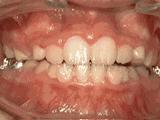

第八种:

前牙反合,俗称“地包天”,也就是咬牙时,下牙盖住上牙,正常情况应该是上牙盖住下牙,经过矫正后的牙齿可以变成这样的~